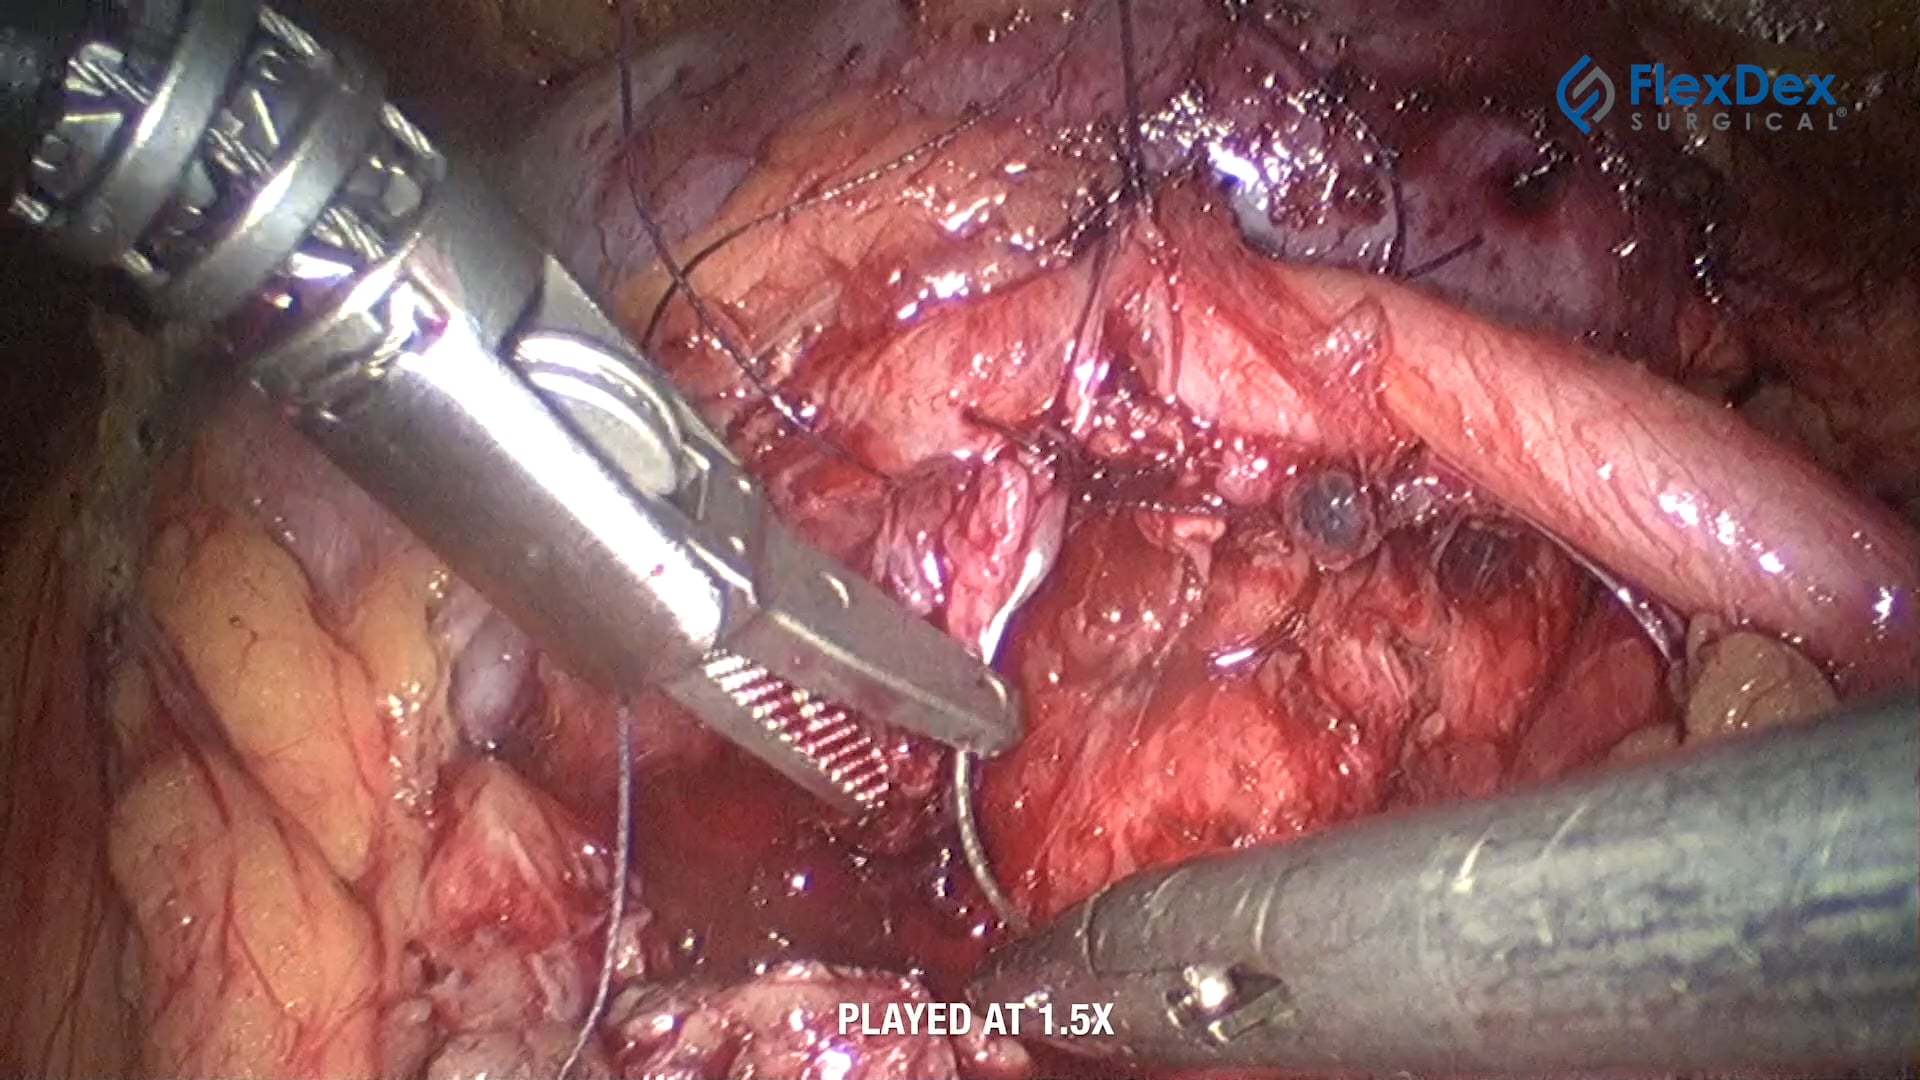

The optimum "Surgeon Powered" articulated needle Driver.

FlexDex’s platform technology precisely translates the surgeon’s hand, wrist, and arm movements to the end effector inside the patient's body.

Based on a simple, purely mechanical, and affordable design, FlexDex greatly enhances the capabilities of MIS instruments.